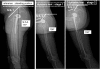

Introduction: The role of the pelvic area in sagittal balance is evident for spinal surgeons, but the influence of the coxofemoral joint is underestimated and inadequately explained by conventional imagery. Comprehensive analysis of the pelvic and subpelvic sectors as part of the sagittal, frontal and cross-sectional balance of the trunk sheds new light on some spinal diseases and their relation to the pelvis.

Results: Disturbances can come from atypical morphotypes or from unusual postures as in aging spine. The measurement of available extension and the concept of available flexion provide new information regarding individual's adaptation to the imbalance induced by disorders of the spine or lower limbs.